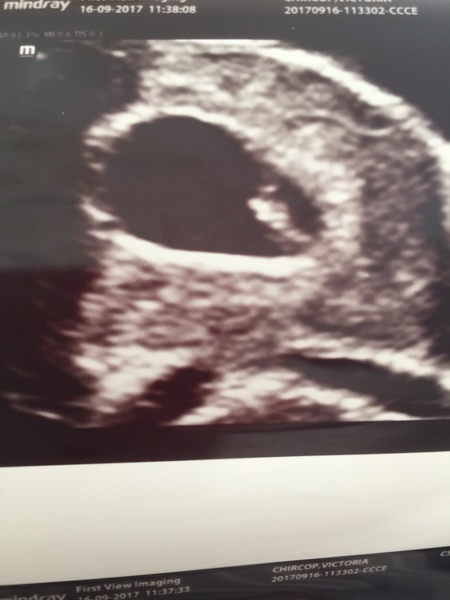

JammyC · 16/09/2017 13:44

Had our scan today, all well but measuring 5 days behind where I thought I was giving an EDD of 4th may! Will see what 12 wk scan says.

Took DD with us to the scan who was asking a million questions so I'm sure it'll only be a matter of time before she says something to someone!

Had my 12 week scan today, will post a pic later. Baby was facing us so had the little alien look instead of the side profile. Due date brought forward to March 28th but I like it here so will stick around. Was a lovely experience, legs and arms were fluttering about. Can't wait to start feeling those movements, was 19 weeks last time before I felt a thing! I'm almost 13 now and I've heard it's sooner on the second.